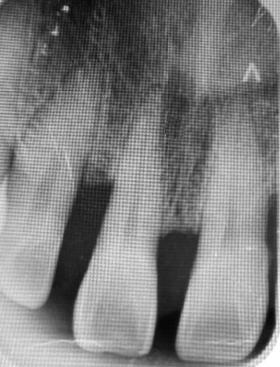

Figura 1. Ortopantomografía.

Figura 2. Radiografías periapicales de órganos dentarios con posibilidad de mantenerse en boca.

hace 8 años por lo que toma 30 mg de nifedipino cada 12 horas, amlodipino 5 mg cada 24 horas, telmisartan 40 mg cada 12 horas y metropolol 100 mg cada 12 horas, además comenta padecer diabetes mellitus tipo II desde hace 7 años por lo que también toma 50 mg de metformina cada 12 horas y dapagliflozina 10 mg cada 24 horas. Clínicamente se observó una encía roja y sangrante, profundos sondeos, una notable hiperplasia gingival, depósitos de cálculo y movilidad dental grado III en todos los órganos dentarios a excepción del segundo premolar superior derecho al canino superior izquierdo, quienes presentaban una movilidad grado II. Radiográficamente se encontró una pérdida de inserción radiográfica avanzada generalizada

en la arcada inferior, y grupos molares de ambos cuadrantes superiores (Figura 1), los únicos órganos dentarios con posibilidad de preservación en boca a través de terapia periodontal se encontraron en el sector anterior de la arcada superior anteriormente mencionados con movilidad grado II

(Figura 2). Por lo que se diagnostica con periodontitis generalizada, estado IV, grado C (Figura 3).